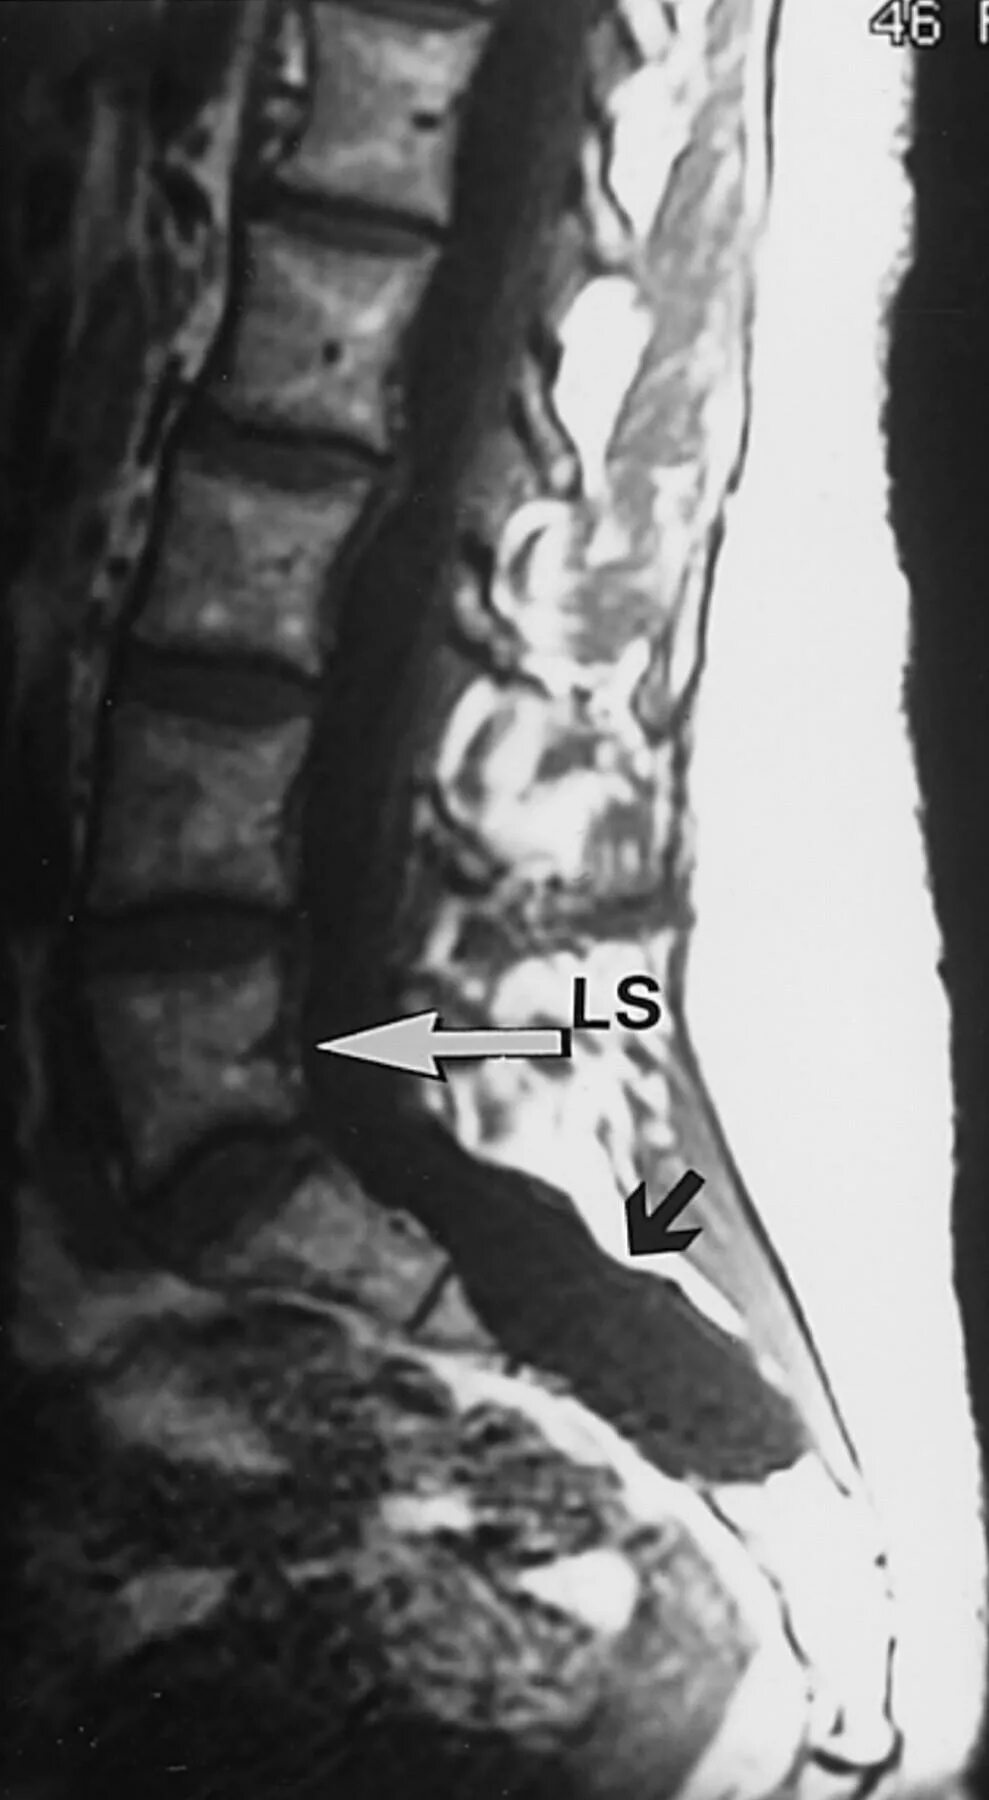

Протрузия в дуральном